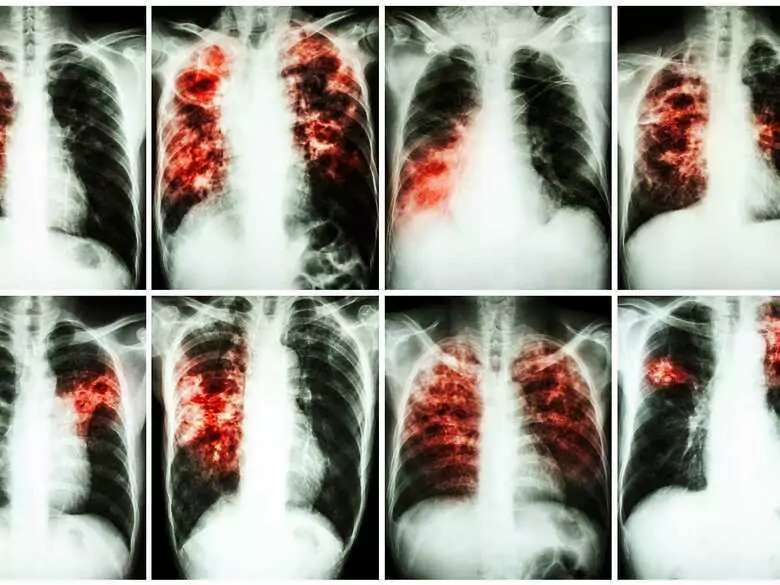

Researchers from the Hradec Králové medical faculty of Charles University in Prague have invented a new drug against tuberculosis. The drug has been sold to an American pharmaceutical company, which will contractually develop the specific. The Prague university will, however, share financially in the proceeds from the sale of the drug.